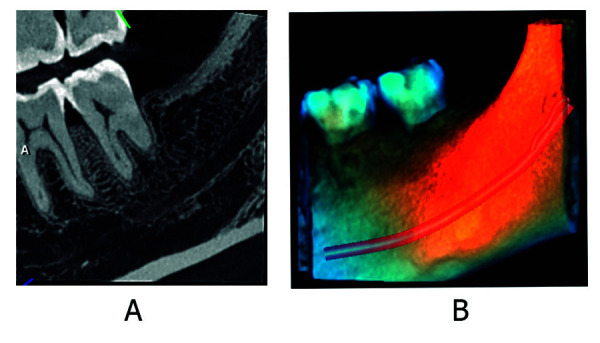

Abstract Image